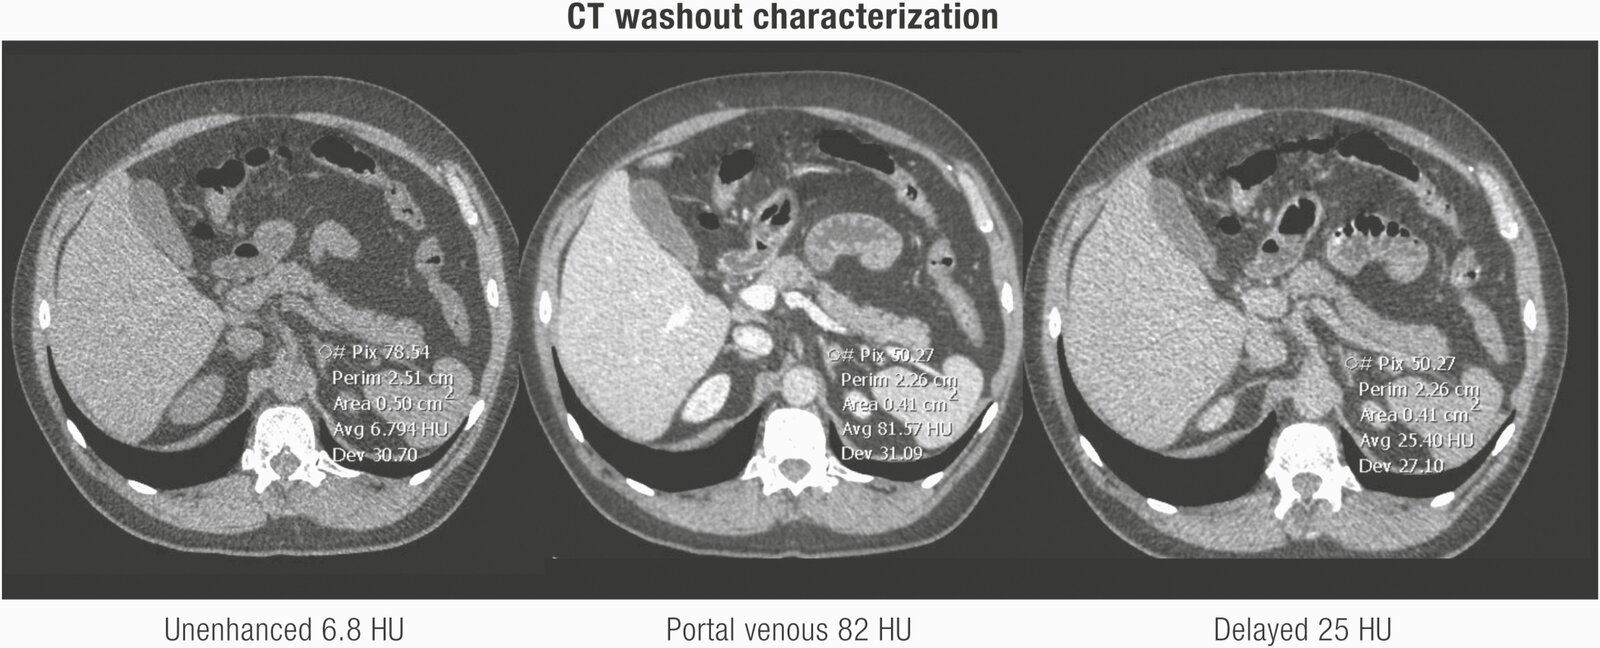

CT without contrast (first-line)[2]

• Low-risk features for malignancy include:

• ≀ 10 Hounsfield units (HU), i.e., lipid-rich mass

• Interpretation

• Low-risk features: no further imaging required

• Combination of low-risk and high-risk features: Consider additional imaging studies.

• High-risk features : Consider surgery (and/or additional imaging).

A homogeneous adrenal mass with an attenuation (radiodensity) of ≀ 10 HU is considered benign and does not require further imaging.

• Other: e.g., MRI , CT abdomen (adrenal washout study) [2]